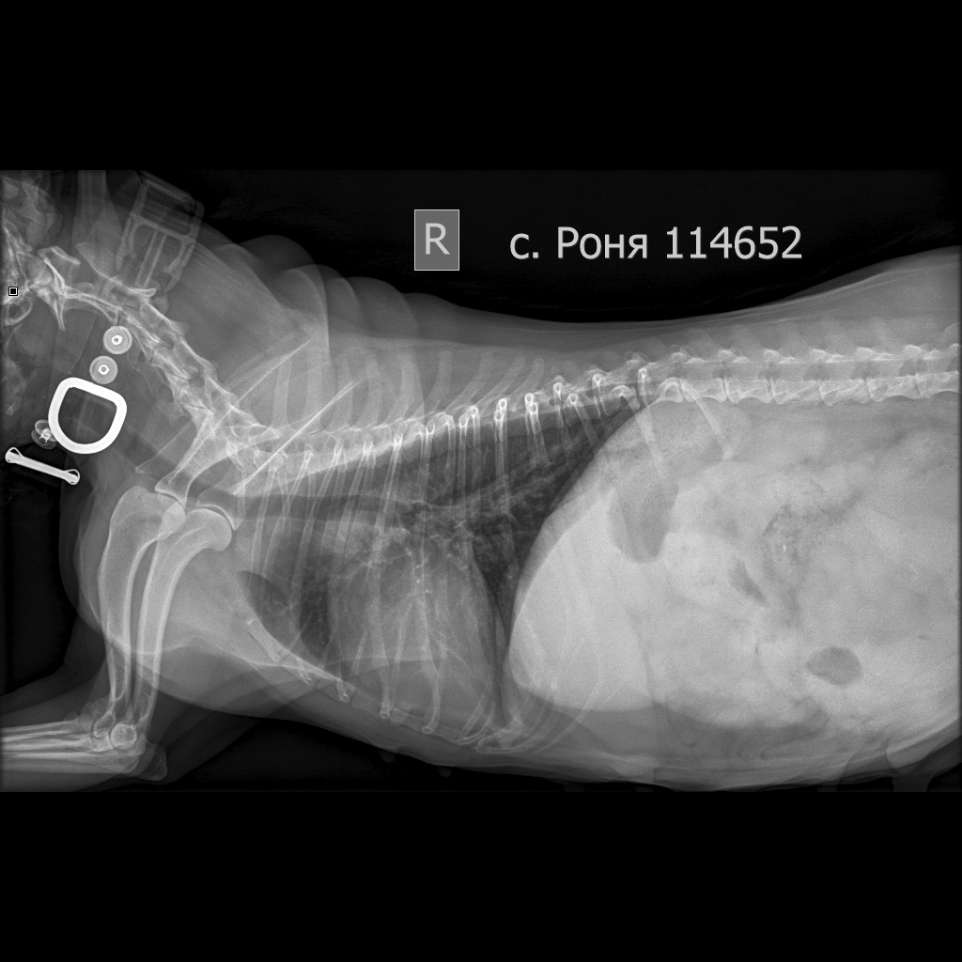

Рентген в двух проекциях и бак посев из раны